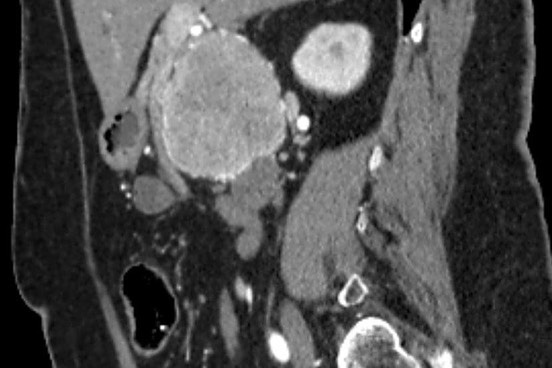

«Միքայելյան» համալսարանական հիվանդանոցում հերթական բարդ վիրահատությունն է իրականացվել, հեռացվել է ենթաստամոքսային գեղձի գլխիկի մեծ ուռուցք ավելի քան 10սմ տրամագծով, որը սերտ հպված էր միջընդերային զարկերակին և երակին:

Առհասարակ ենթաստամոքսային գեղձի գլխիկի մեծ չափի ուռուցքները համեմատաբար քիչ են հանդիպում: Առավել քիչ են հանդիպում այն դեպքերը, երբ գեղձի գլխիկի մեծ չափերի ուռուցքը չի առաջացնում մեխանիկական դեղնուկ: Համալսարանական հիվանդանոցի Վիրաբուժության կլինիկա է դիմել 62 տ. կին՝ գանգատվելով ցավից և ծանրության զգացումից վերորովայնային (էպիգաստրալ) շրջանում:

Կատարվել է պանկրեատոդուոդենալ մասնահատում, տեխնիկական դժվարություններով ուռուցքն անջատվել է վերին միջընդերային երակից և զարկերակից:

Հեռացված հյուսվածքի հետազոտությամբ հայտնաբերվել է ենթաստամոքսային գեղձի գլխիկի նեյրոէնդոկրին ուռուցք: